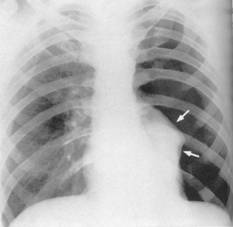

Fig.77 Pleurezia incipienta

Uneori unicul semn al pleureziei este ingrosarea scizurilor interlobare.

O cantitate minima de lichid in sinusul costodiafragmatic posterior poate trece neobservat pe radiografia de fata, lichidul fiind mascat de diafragm. Acesta poate fi pus in evidenta pe o radiografie de profil cu tubul lateral, incidenta in care sinusul posterior nu mai este mascat de umbra hepatica ca pe imaginea de fata.

Lichidul devine vizibil pe o radiografie de fata, in ortostatism la cantitati de 250-600 ml.

Radiologic: opacitate omogena, de intensitate cu atat mai mare cu cat cantitatea de lichid este mai mare; delimitata net si care ocupa sinusul costo diafragmatic. In Trendelenburg, cantitatea mica de lichid de la baza migreaza intre foitele pleurale si opacifiaza varful pulmonului respectiv, aceasta manevra putand sa faca diagnosticul diferential intre o pleurezie minima si o ingrosare pleurala sechelara.